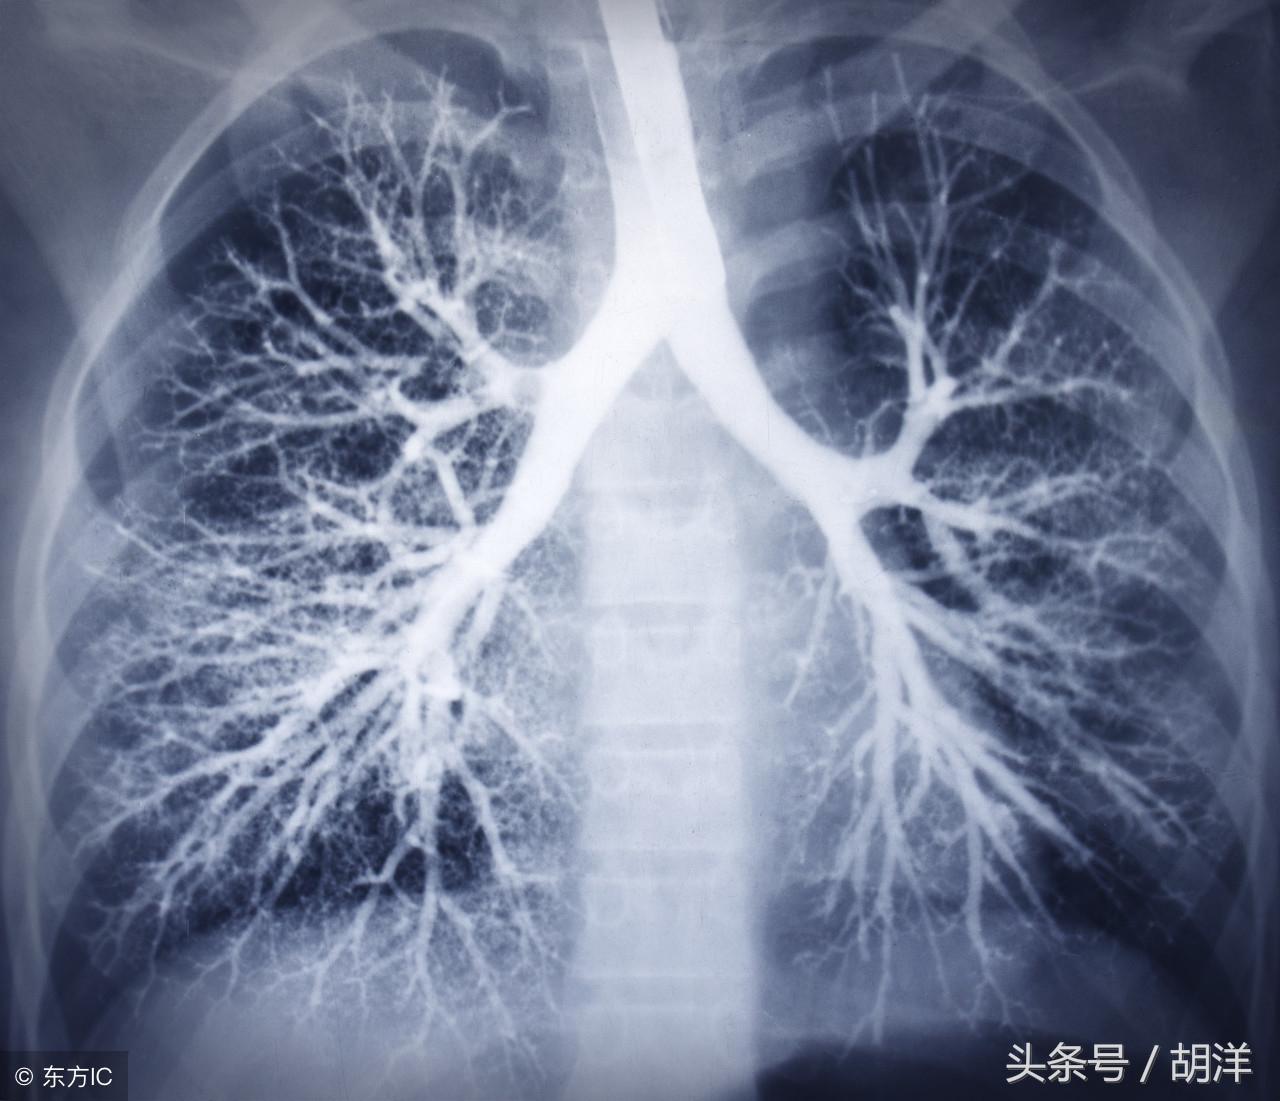

咳血又称咯血,是呼吸科一个比较严重的症状,由于其可能提示肺部肿瘤等严重疾病而受到重视,但事实上在引起咯血的病因中,肺部恶性肿瘤所占的比例并不是很大,但很多人因咯血而焦虑异常,特别是咯血久治不愈情况下,更加令人无法正常的生活和学习,那么哪些疾病可能导致反复发作痰中带血或者咳出满口鲜血呢?

支气管扩张是一种支气管管壁结构破坏性疾病,正常情况下,支气管是一个带有弹性,拥有一定管径的能够维持正常呼吸通气的结构,当管壁结构受到破坏时,气管会受到被动的牵拉而扩张,管壁的血管由于弹性较小,容易被撕扯呈血管瘤改变,一旦胸腔内血流压力增大可能冲破血管瘤变薄的管壁而导致大咯血,少量渗血时则呈现为痰中带血。

肺炎引起咯血的原因和肺结核类似,都是由于肺部细菌感染后破坏正常肺结构引起渗血以及血管破裂所致。